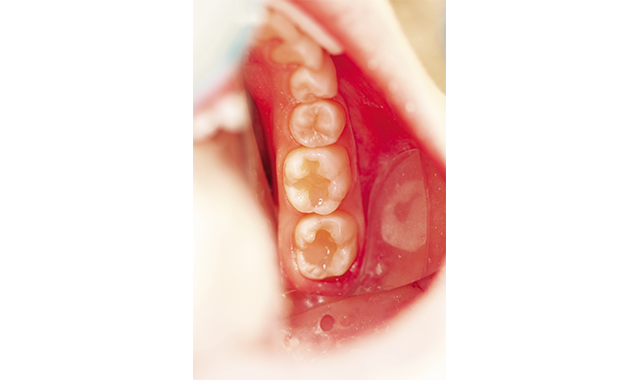

How to perform a void-free restoration

How one dentist uses Tetric EvoLine bulk fill materials to provide patients with excellent dentistry.

by Jason Olitsky, DMD, AAACD

Featured product: Tetric Evoline Bulk Fill from Ivoclar Vivadent

Posterior restoratives are required to meet many criteria to be clinically successful. As practitioners, we strive to meet these criteria in every case despite the unique and individual challenges presented by each tooth and patient.